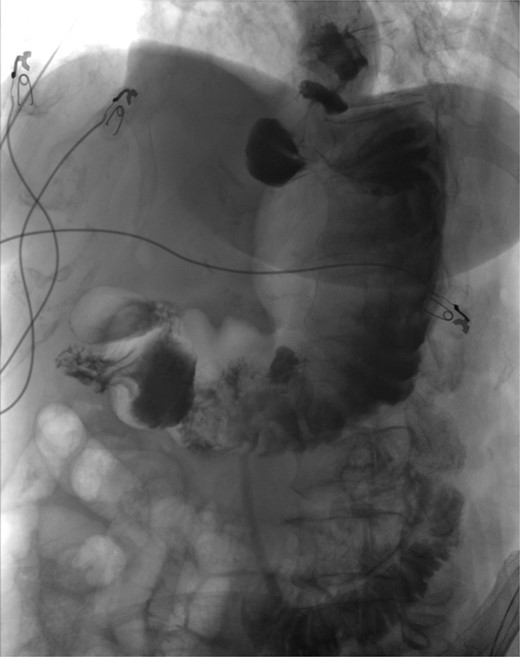

The patient was a 74-year-old female with a history of hypertension, chronic migraines, hiatal hernia repair with Nissen fundoplication repair, and cecal volvulus treated with right hemicolectomy who presented with abdominal pain, nausea, and vomiting. Six months prior, she exhibited symptoms of bloating and nausea, which were treated with oral Reglan with some improvement. She reported vomiting episodes for 2 months that acutely worsened over the 4 days prior to presentation. Examination revealed a soft and mildly distended abdomen with tenderness in the epigastrium and left upper quadrant. Initial vital signs showed a temperature of 36.1°C, blood pressure of 149/88 mmHg, heart rate of 115 beats/min, and oxygen saturation of 95% on room air; tachycardia resolved with resuscitation. Labs were notable for a white blood cell count of 8.8 × 1000/mcL and hemoglobin of 14.2 g/dL. Sodium was 137 mEq/L, potassium was 3.3 mEq/L, and creatinine was 0.75 mg/dL. Computed tomography (CT) of the abdomen and pelvis (Figs 1 and 2) showed gastric volvulus without pneumatosis, significant wall thickening, or distention. Nasogastric tube was placed. An upper gastrointestinal fluoroscopy scan showed no passage of contrast beyond the stomach and demonstrated 90° rotation of the stomach (see Fig. 3). The patient underwent surgery that same day.

Upper GI study demonstrating no passage of contrast beyond stomach and 90° rotation.